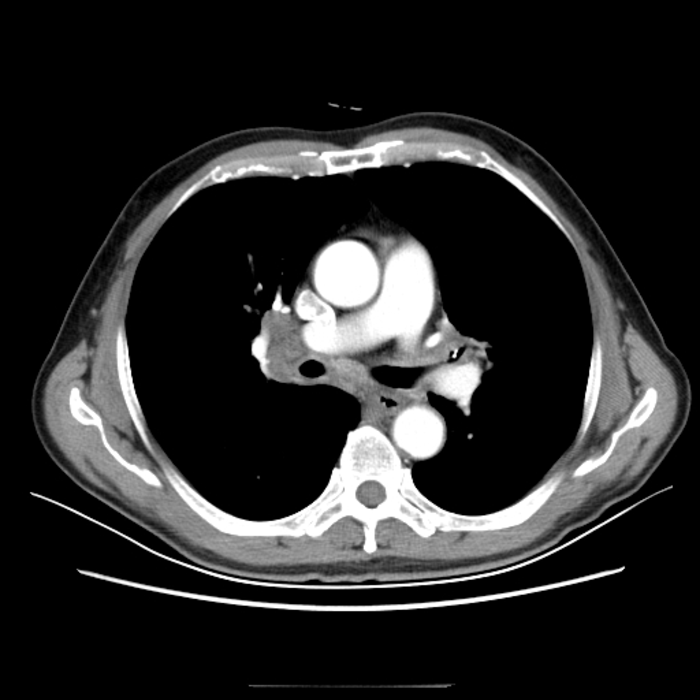

病例5

患者男,68岁,因“咳嗽伴发热15天“入院。

辅助检查:血常规正常。胸部CT报告:1、右肺上叶少许炎性灶伴局部支气管轻度扩张;2、右肺中叶偏小伴少许不张,请结合支气管镜;3、右肺中叶、左肺散在炎症;4、右肺上叶、左肺下肺囊肿;5、冠脉钙化。

为了进一步明确,我们做了支气管检查,镜下发现支气管出现“惊奇”的一幕——气管、支气管黏膜下有多发性骨质或软骨组织结节状增生并突向管腔。

图12

看到这种病变是不是觉得很惊奇?能看出这是什么病吗?其实,这种病变常见于“骨化性气管支气管病”“气管支气管淀粉样变”等少见病。

我们再回看这个胸部CT的纵膈窗可以发现气管明显有气道壁后方膜部不受累的环状高密度影(钙化灶)。

图13

因为慢性气管支气管炎、老年性气管支气管等情况也可出现类似改变,很多人感觉司空见惯或认识不足常常不注意而漏诊。

我们在支气管镜下行活检,病理回报符合“骨质沉着性气管病”——即“骨化性气管支气管病”诊断成立。

图14